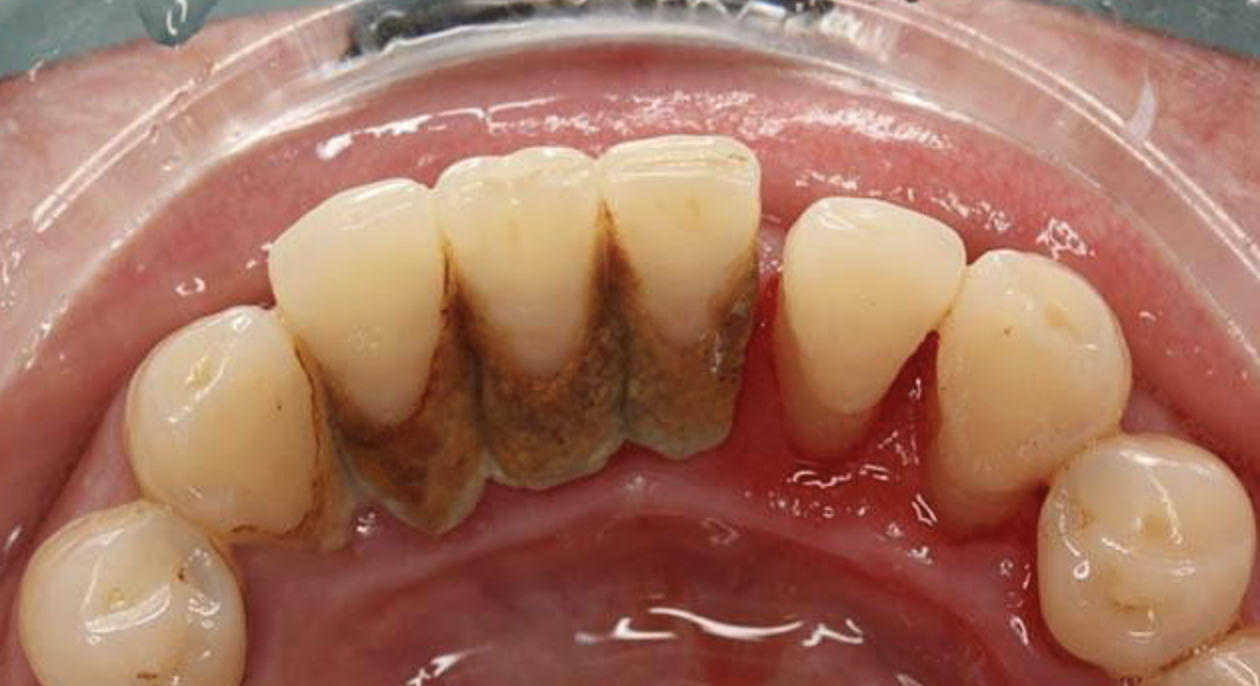

麦芽口腔指出,生活中常见的牙龈出血都是牙性的,没有全身性的不适,表现为刷牙、进食、吸吮时牙龈出现渗血。导致牙龈出血的原因除了硬物撞击导致的牙龈受伤,更多是口腔卫生引起的。

尤其针对牙周炎患者来说,存在牙周袋,牙菌斑与牙结石多附着于龈下,尤其容易导致牙龈炎症。